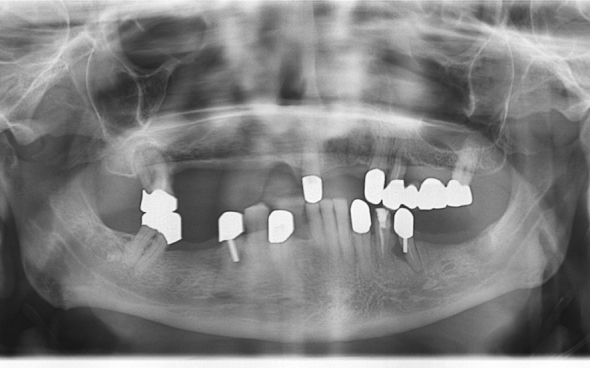

Metallkeramische Oberkiefer- und Unterkiefer-Vollbrücken

Der 48 jährige österreichische Patient erschien an unserer Zahnklinik zu einem Beratungstermin, wo eine Röntgenaufnahme und ein Kostenplan für metallkeramische Vollbrücken im Ober- und Unterkiefer mit insgesamt 25 Kronen erstellt wurden.